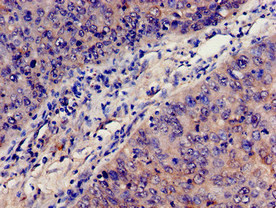

Immunohistochemistry analysis of human cervical cancer using CSB-PA10599A0Rb at dilution of 1:100